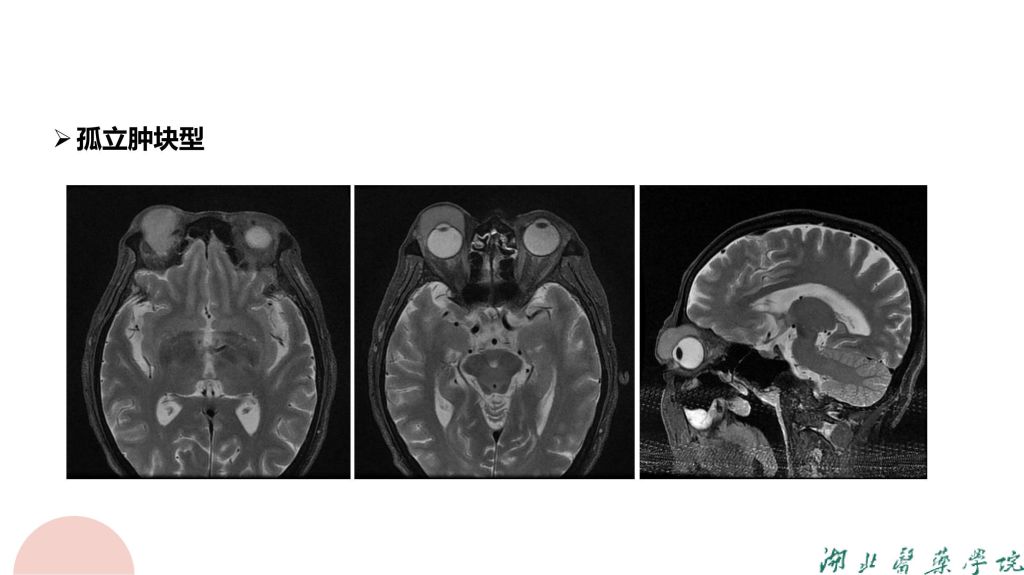

病例分析-眼眶淋巴瘤